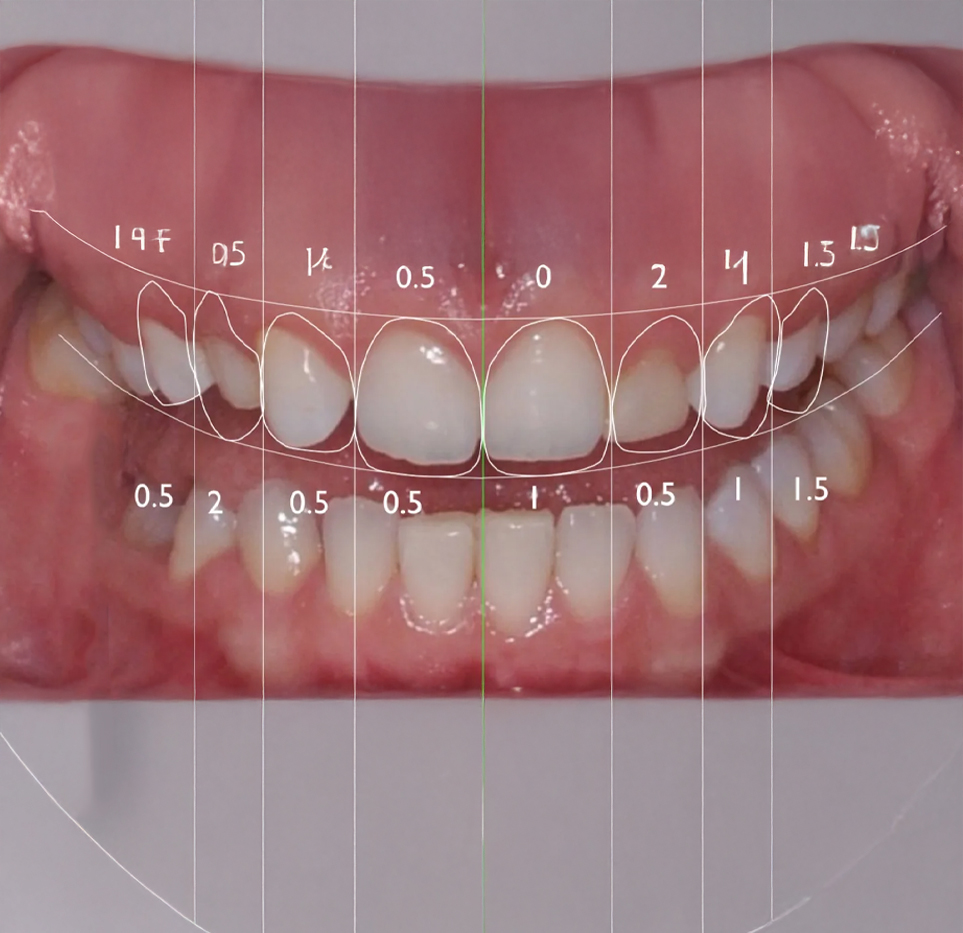

Dijital Gülüş Tasarımı (DSD), herhangi bir diş tedavisine başlanmadan önce hastanın ideal gülüşünü planlamak amacıyla dijital teknolojilerin kullanıldığı modern bir kozmetik diş hekimliği yaklaşımıdır. Bilgisayarlı görüntüleme yazılımları ve ileri dijital araçlar sayesinde ağız ve dişlerin üç boyutlu bir temsili oluşturulur. Bu yöntem, diş hekiminin planlanan estetik diş tedavisinin sonucunu önceden görselleştirmesine olanak tanıyan, sanat ve bilimin birleştiği bir uygulamadır.

Süreç genellikle diş hekiminin hastanın dişleri ve yüz yapısına ait fotoğrafları, videoları ve diğer dijital kayıtları almasıyla başlar. Elde edilen görüntüler, özel yazılımlar aracılığıyla analiz edilerek hastanın yeni gülüşünün dijital bir taslağı oluşturulur. Bu taslak, hasta önerilen sonuçtan memnun kalana kadar düzenlenebilir ve ince ayarlamalar yapılabilir.

Diş hekimi, özel kameralar ve yazılımlar kullanarak hastanın dişlerinin ve yüz yapısının dijital fotoğraflarını ve videolarını alır. Bu veriler, ağız ve dişlerin üç boyutlu bir modelinin oluşturulmasında kullanılır.

Elde edilen dijital görüntüler, özel yazılımlar aracılığıyla analiz edilerek hastanın yeni gülüşü tasarlanır. Bu aşamada dişlerin şekli, boyutu ve rengi belirlenirken yüz estetiği de dikkate alınır.